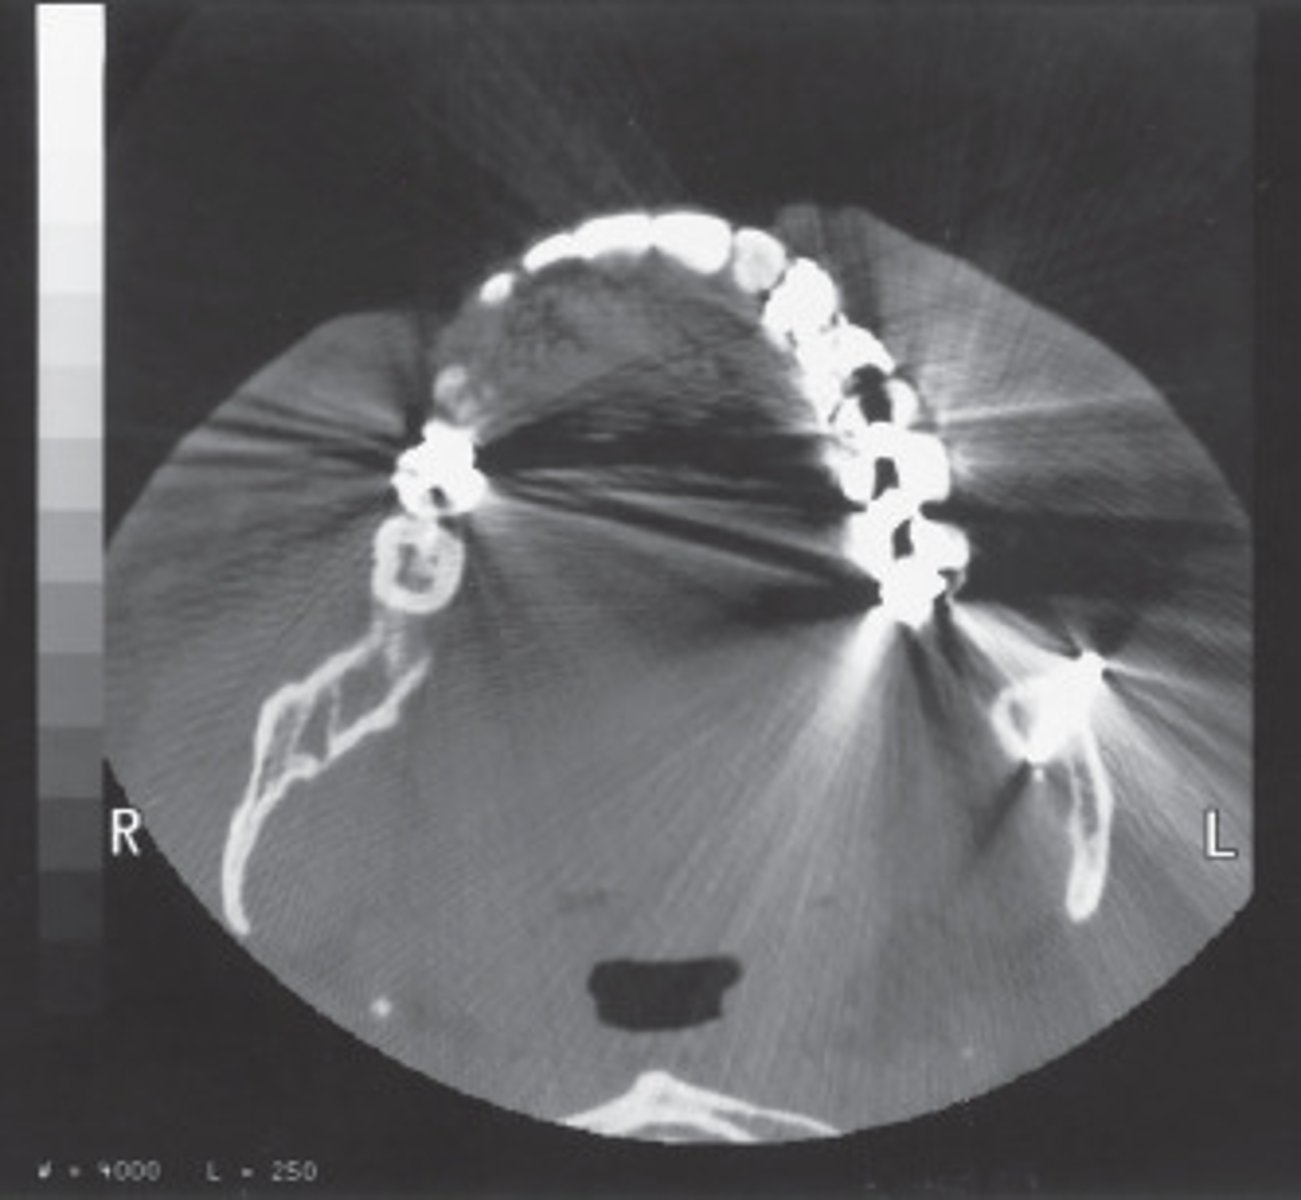

These streaking artifacts were most likely caused by:

<p>These streaking artifacts were most likely caused by:</p>

0 degrees;

The Azimuth setting refers to the relationship betyween the x-ray tube and detectors during scout of localizer production.

What azimuth setting was used to obtain this image?

<p>What azimuth setting was used to obtain this image?</p>